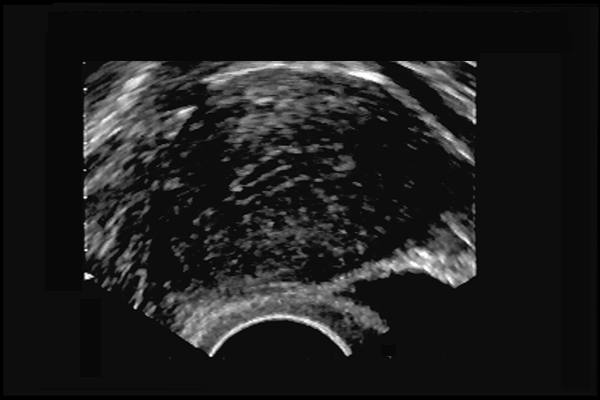

Adénomyose utérine. Myomètre hétérogène - flammèches d'endomètre vers le myomètre (+). 43 ans, ménorragies.